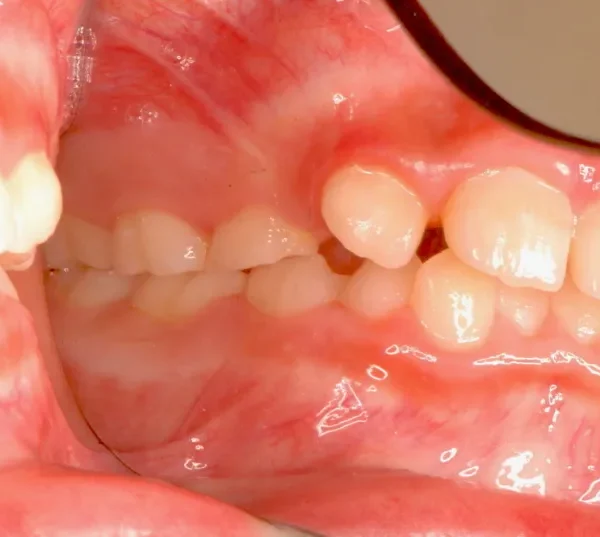

初診時年齢 小学校3年生 (男性) 主訴 前歯がゆがんでいる・ガタガタ

診断名 叢生・交叉咬合 装置名

上下の幅が狭くガタガタに生えています。

初診